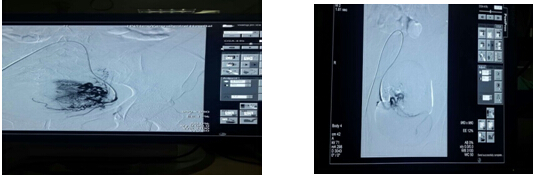

子宮動(dòng)脈栓塞前供血豐富 子宮動(dòng)脈栓塞后血管堵塞

我院腫內(nèi)一區(qū)率先開展了子宮肌瘤的全新微創(chuàng)治療方法——子宮動(dòng)脈栓塞術(shù), 即經(jīng)皮股動(dòng)脈穿刺,在X線造影下,通過微導(dǎo)管將栓塞劑置入提供子宮肌瘤的雙側(cè)子宮動(dòng)脈,阻斷肌瘤的血液供應(yīng),斷其”糧草”,使肌瘤缺血缺氧而發(fā)生壞死、變性,甚至脫落、消失的一種新型治療技術(shù)。此手術(shù)顛覆了傳統(tǒng)“開刀切除肌瘤”的方式,能夠在不傷害子宮的情況下治愈肌瘤,取得良好的治療效果,深受患者的追捧,目前我科已成功為200多名子宮肌瘤患者實(shí)施微創(chuàng)手術(shù),解除病痛。

近日,家住衡南縣花橋鎮(zhèn)的王女士因體檢發(fā)現(xiàn)子宮粘膜下肌瘤9月,月經(jīng)增多3月前來我科就診.磁共振示肌瘤約50 *46 *30mm。如此大的肌瘤顯然不適合做宮腔鏡,而手術(shù)開刀無疑是“傷宮”治療。唐玉成主任和陽(yáng)美玲副主任憑借多年精湛的介入技術(shù),僅用一根導(dǎo)管,只花費(fèi)30分鐘就將肌瘤供血血管堵住,治療后僅留下約1~2mm小切口,術(shù)后患者只需下肢制動(dòng)12小時(shí),就能下地活動(dòng),觀察3天患者便康復(fù)出院了。